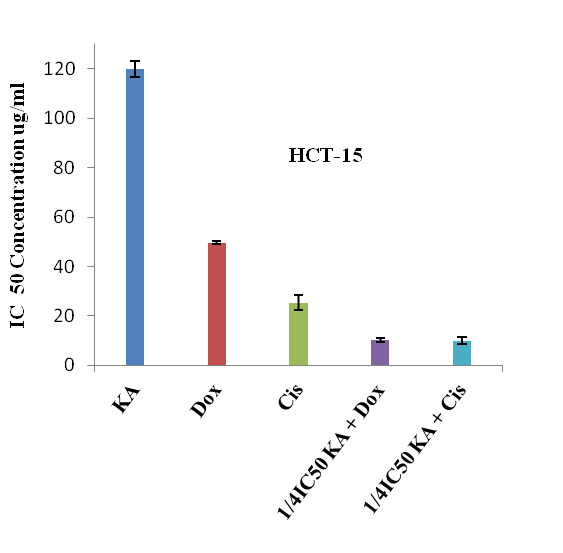

Combination effect of kaempferol and chemotherapeutic drugs on cell growth

The combination effect of kaempferol with doxorubicin or cisplatin in the HCT-15 and MDA MB 231 cell lines has been represented in CI and the results are summarised. The data was examined using median effect analysis to determine the type of interactions which occurred, i.e., antagonism (CI>1), additivity (CI=1) or synergism (CI<1) (table 3).

The CI values for HCT-15 and MDA MB 231, when treated with kaempferol in combination with doxorubicin/cisplatin, were 0.45 and 0.65, 0.55 and 0.65 respectively, where CI<1 means synergism, CI=1 means additive effects and CI>1 means antagonism. In all combination treatments, the concentrations of doxorubicin and cisplatin necessary to inhibit 50% of cancer cells (IC50) were reduced by 5 and 2.5 fold for HCT-15 and 2.4 and 2.6 fold for MDA MB 231 respectively. To assess the effect of kaempferol and doxorubicin or cisplatin on HCT-15 and MDA MB 231 cell growth, cells in the exponential growth phase were treated with different doses of kaempferol (5, 10, 25, 50, 100 and 150 µg/ml), doxorubicin (5, 10, 25 and 50 µg/ml) and cisplatin (5, 10, 25 and 50 µg/ml) for 24 h. At the end of the treatment, the determination of % cell death showed that these agents inhibited cell growth in a dose-dependent manner. On the basis of these results, experiments were performed on both the cell lines (for 24 h) by combining kaempferol at 30 µg/ml (1/4 IC50) with doxorubicin/cisplatin at 5, 10, 25 and 50 µg/ml for HCT-15 (fig. 5). The experiment was repeated for MDA MB 231 cells by considering the concentrations of kaempferol with doxorubicin/ cisplatin as 32 µg/ml (1/2 IC50) and 5, 10, 25 and 50 µg/ml respectively (fig. 6). At the end of the experiments, significant synergistic growth inhibition of both HCT-15 and MDA MB 231 was observed.

The increase in systemic toxicity and drug resistance are the major drawbacks of cancer chemotherapeutic agents are led to a new challenge in the field of cancer research. To overcome this problem, extensive research has been directed towards reducing systemic toxicity and increasing drug activity in cancer therapy [2]. In this regard, combination therapy has received more attention for the purpose of finding compounds with a known mechanism of action that could increase the therapeutic index of clinical anticancer drugs [17]. The above results indicate that the in vitro therapeutic effect of doxorubicin in terms of cell growth inhibition at the 49.6±0.5 µg/ml dose was achieved at its one-fifth concentrations (10.2±0.83 µg/ml) in combination with 30 µg/ml dose of kaempferol in HCT-15 cells whereas with cisplatin, cell growth inhibition at 25.4±2.9 µg/ml was achieved at its half concentration (10±1.34 µg/ml dose) in combination with 30 µg/ml dose of kaempferol.

However, phytochemical kaempferol and therapeutic drugs doxorubicin and cisplatin showed the cytotoxic effect on HCT-15 cells individually at 120±3.2 µg/ml, 49.6±0.5 µg/ml and 25.4±2.9 µg/ml respectively. Simultaneously, on MDA-MB 231 cell line, the in vitro therapeutic effect of doxorubicin and cisplatin was achieved at 44±1.8 µg/ml and 40.6±0.8 µg/ml was reduced to 18±1.22 µg/ml and 15±1.87 µg/ml in combination with 32 µg/ml dose of kaempferol.

Fig. 5: IC50 Concentrations of kaempferol, doxorubicin and cisplatin alone and in combination on human colon cancer cells (HCT-15). KA-Kaempferol, Dox-Doxorubicin, Cis-Cisplatin, n=5